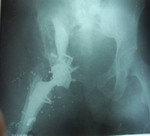

Քացախափոսը մշակվեց և տեղադրվեց պրոթեզի քացախափոսային կոմպոնենտը` ֆիքսելով այն 5 պտուտակներով: Կեղծ քացախափոսըլրացվեց և ամրացվեց ոսկրային ցեմենտով (նկ. 3):

Նկ. 3. Այնուհետև աջ ազդրոսկրի ս/3-ի կոտըրվածքը համադրվեց և ֆիքսվեց մետաղականհարթակով:

Մ/3-ականի մակարդակում ոսկրաբեկորները համադրվեցին և ֆիքսվեցին 2 մետաղական ամրաթելերով, իսկ տամբիոնների շրջանում` 3 մետաղական պտուտակներով:

Աջ ազդրոսկրի խողովակը մշակվեց և ազդրային կոմպոնենտը տեղադրվեց: Հոդախախտը ուղղվեց, կատարվեցին ստուգիչ շարժումներ և հյուսվածքները շերտառ շերտ վերականգնվեցին (նկ. 4):